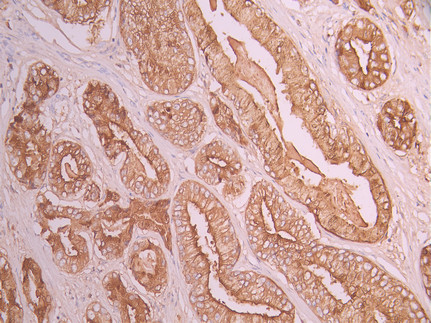

• IHC image of CSB-RA255091A0HU diluted at 1:100 and staining in paraffin-embedded human prostate cancer performed on a Leica BondTM system. After dewaxing and hydration, antigen retrieval was mediated by high pressure in a citrate buffer (pH 6.0). Section was blocked with 10% normal goat serum 30min at RT. Then primary antibody (1% BSA) was incubated at 4°C overnight. The primary is detected by a Goat anti-rabbit polymer IgG labeled by HRP and visualized using 0.05% DAB.